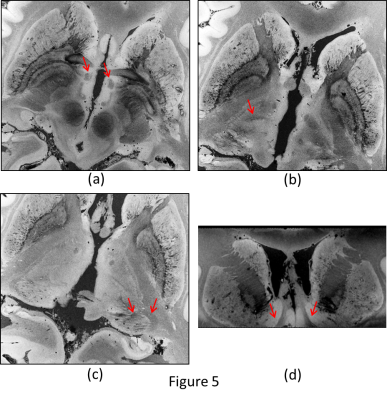

Previous work with ex vivo imaging has been done using a sophisticated process. The results shown here suggest that similar data(200um resolution) can be readily acquired without taking extraordinary or costly measures.

Figure 5. Different slices of 200um resolution image. (a) Axial. Fascicles in the Fornices. (b) Axial. Thalamic Nuclei.(c) Axial. LGN and adjacent optic radiation. (d) Coronal. Nucleus Accumbens